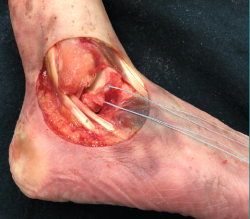

3. Finalmente, realizamos la reparación anatómica directa del LTFA.

Esta técnica consiste en la reinserción del resto ligamentoso con 2 anclajes. Tras la identificación de la huella ósea en el peroné, pasamos 2 puntos de una sutura reabsorbible de alta resistencia FiberWire® de #2/0 (Arthrex Inc., Naples, FL) ayudándonos de un Micro SutureLasso® de 70° (Arthrex, Naples, FL) a través de los restos del LTFA (Figura 4). La guía de broca se sitúa en la huella ósea del LTFA, justo distal a la inserción del ligamento tibiofibular anteroinferior distal (porción más anterior de la sindesmosis tibioperonea) (Figura 5). Posteriormente, se pasa cada sutura a través de un anclaje sin nudo Bio-PushLock® de 2,5 mm (Arthrex, Naples, FL) y se introduce la sutura más distal en el orificio más distal (Figura 6). Durante la implantación de los anclajes se debe mantener una posición fija del pie en flexión neutra y eversión de 5-10°. Se repite la misma operación con el segundo punto de sutura, el más proximal en el orificio más proximal. El empleo de 2 anclajes permite una mayor superficie de contacto del LTFA con el hueso, así como una mejor distribución de las tensiones, desde un punto de vista biomecánico. Esta técnica artroscópica ya ha sido descrita por Arroyo en el año 2017(10).

Figura 6. Reparación directa del ligamento talofibular anterior con 2 implantes biodegradables Bio-PushLock® de 2,5 mm (Arthrex, Naples, FL). Aspecto final de la reparación.